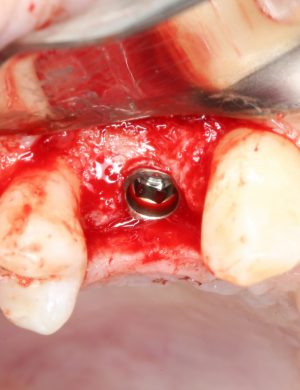

После перкуторной проверки стабильности имплантатов и точности позиционирования, мы переходим к следующему этапу — сохранению десневого контура.

Установка имплантатов занимает около двух минут.

Сохранение десневого контура

Для этого мы используем индивидуализируемые временные абатменты Esthetic Cap треугольного сечения, являющиеся уникальной разработкой Xive. Об их преимуществах для решения подобных задач можно прочитать здесь>>, а тема формирования и сохранения десневого контура подробно раскрыта тут>>. Очень рекомендую прочитать.

Абатменты позиционируются в трех положениях, потому мы заранее выровняли платформу по граням. Усилие, с которым устанавливаются абатменты, не превышает 10-14 Нсм.

На этом хирургический этап лечения заканчивается.

Мы сделали рентгеновские контрольные снимки —  панорамный для оценки положения имплантатов и прицельный для контроля посадки абатментов.